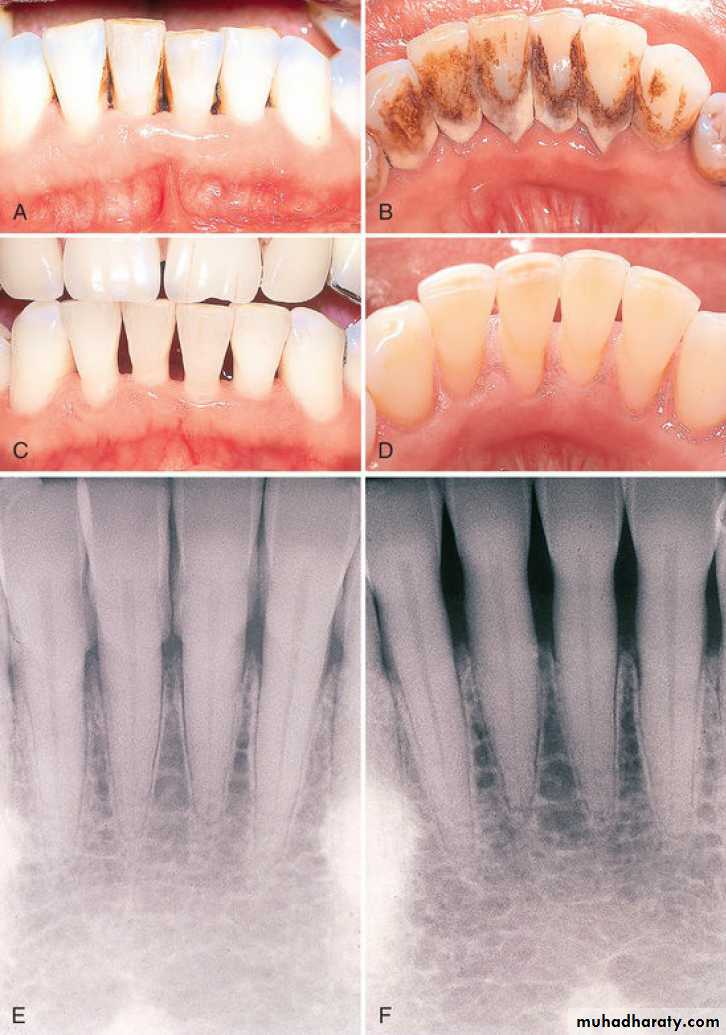

Scaling is the process by which biofilm and calculus are removed from both supragingival and subgingival tooth surfaces. Root planing is the process by which residual embedded calculus and portions of Cementum are removed from the roots to produce a smooth, hard, clean surface.

Scaling and root planing are not separate procedures; all the principles of scaling apply equally to root planing.

The primary objective of scaling and root planing is to restore

gingival health by completely removing elements that provoke

gingival inflammation (i.e., biofilm, calculus, and endotoxin) from

the tooth surface

• When biofilm and calculus form on enamel, the deposits are usually superficially attached to the surface and are not locked into irregularities.

• Scaling alone is sufficient to completely remove biofilm and calculus from enamel, leaving a smooth, clean surface.

• Root surfaces exposed to biofilm and calculus pose a different problem. Deposits of calculus on root surfaces are frequently embedded in cemental irregularities.

• Subgingival calculus is porous and harbors bacteria and endotoxin and therefore should be removed completely